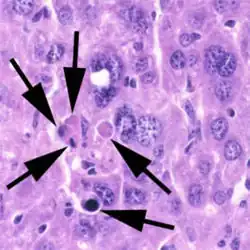

In pathology, a Councilman body, also known as a Councilman hyaline body or apoptotic body, is an eosinophilic globule of apoptotic hepatocyte cell fragments. Ultimately, the fragments are taken up by macrophages or adjacent parenchymal cells.[1] They are found in the liver of individuals suffering from acute viral hepatitis, yellow fever, and other viral syndromes.[2]

Councilman bodies were first identified in yellow fever, which characteristically shows a midzonal hepatic necrosis on biopsy. Similar inclusions are observed in other viral hemorrhagic fevers and all of the viral hepatitides. Liver biopsy of acute viral hepatitis shows panlobular lymphocytic infiltrates with ballooning hepatocytes.[4]

Hepatocytes are the liver's primary parenchymal cells, forming 80% of the liver's mass and 60% of its cells. They are round in shape and contain a nucleus and organelles that contribute to metabolic and secretory functions.[5] Hepatocytes also play a pivotal role in liver inflammation.[6] Councilman bodies are often named for the hepatocytes undergoing apoptosis, which occurs in the portal tracts and lobules of the liver. Inflammation of the liver is caused by the cytotoxic killing of hepatocytes, or Councilman bodies. Eventually, this inflammation leads to liver damage in viral hepatitis.[7] Through the use of double immune fluorescence methods, HBsAg and/or HBcAg (hepatitis B core antigen) are present in Councilman bodies in the liver.[8]

With a bright field microscope, Councilman described typical, discrete, necrotic lesions in human hepatic cells of those infected with yellow fever.[9] He noted that the bodies appeared to be red in hematoxylin and eosin-stained sections of hepatic tissue, while being circumscribed, varying in size, round or irregular shape, and having numerous vacuoles of different sizes.

Five adults with hepatitis, two children with hepatoma, and three mongrel dogs provided tissue samples for study have an auxiliary liver transplant into the pelvis. The tissues were fixed immediately in ice-cold 1% osmium tetroxide, buffered with veronal acetate, and sucrose. Sections were cut, stained with lead hydroxide or citrate, and viewed under an electron microscope. The results showed the both canine and human tissue were intact, but altered hepatocytes were observed.[11] The doctors declared that councilman bodies were observed as vacuolated acidophilic bodies within the tissue samples.

An LEC rat, an inbred mutant rat, which suffered from hereditary hepatitis, was examined for elucidation during the development of the acute phase of hepatitis by quantitative analyses of the liver and laboratory data on serum enzymes. The progression of the acute hepatitis in the LEC rat was observed, showing only a few enlarged hepatocytes and Councilman bodies in its early life. These appeared around 8 weeks of age without any clinic signs of hepatitis. The acute phase of hepatitis started with a major increase of Councilman bodies, large nuclei, and hepatocytes in mitosis in the liver around 3-4 weeks before the onset of fulminant hepatitis. From these observations, three stages of progression of acute hepatitis were proposed in the LEC rat.[12]